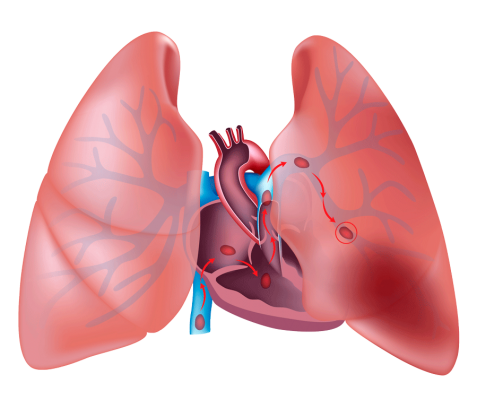

El diagnóstico de tromboembolismo pulmonar es una tarea notoriamente compleja debido a la naturaleza solapada de sus síntomas con los de otras condiciones cardiopulmonares. La disnea, o dificultad para respirar, y el dolor torácico, especialmente al respirar profundamente, son síntomas comunes que pueden encontrarse en diversas enfermedades respiratorias y cardiovasculares. Esta superposición de síntomas hace que la EP no siempre sea inmediatamente evidente y requiere una evaluación cuidadosa para diferenciarla de otras patologías similares.

- La tomografía computarizada de tórax con angiografía (CT-PA) helicoidal se ha consolidado como el estándar de oro para el diagnóstico de embolia pulmonar (EP) en América del Norte, gracias a su alta sensibilidad y especificidad, junto con su amplia disponibilidad en los hospitales. Este estudio es particularmente valorado por su capacidad para detectar con precisión la presencia de trombos en las arterias pulmonares, lo cual es crucial para confirmar o descartar una EP.

- El CT-PA se realiza mediante la administración de un tinte radiocontraste intravenoso que permite visualizar las estructuras vasculares del pulmón con gran detalle. Aunque este procedimiento implica la introducción de contraste en el cuerpo, se considera no invasivo en comparación con otros métodos diagnósticos más invasivos como la angiografía convencional. La alta resolución de la imagen proporcionada por la CT-PA facilita la identificación de embolias de distintos tamaños, desde grandes trombos que bloquean grandes arterias pulmonares hasta trombos más pequeños en ramas menores.

- La gammagrafía V/Q evalúa dos aspectos fundamentales de la función pulmonar: la ventilación y la perfusión. En el estudio, se administra un radiofármaco que permite visualizar la distribución del flujo sanguíneo (perfusión) y el flujo de aire (ventilación) en los pulmones. La presencia de un defecto en la perfusión sin un defecto correspondiente en la ventilación puede sugerir una embolia pulmonar, ya que la obstrucción de una arteria pulmonar impide que el contraste llegue a una área del pulmón mientras que la ventilación puede estar intacta.